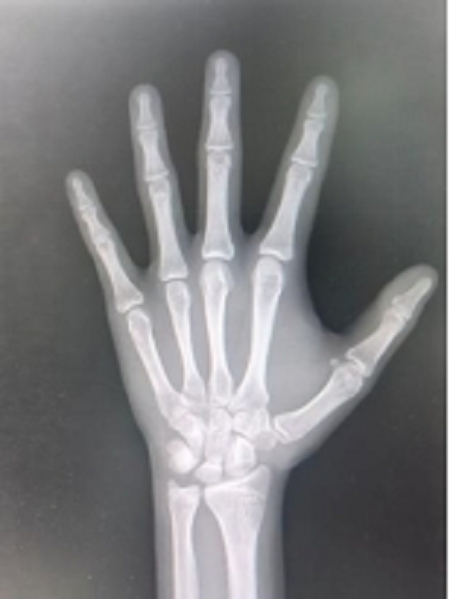

图片3

骨骺线完全闭合状态